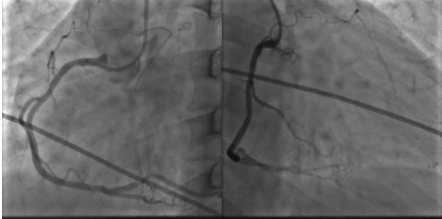

2015年10月23日:左主干远段30%狭窄;左前降支近段支架自开口完全闭塞;左回旋支中段长病变,狭窄40%~50%,高位钝缘支粗大,未见狭窄(图1)。右冠粗大、优势型,近段管壁不规则,左室后支、后降支未见狭窄(图2、3)。

图1